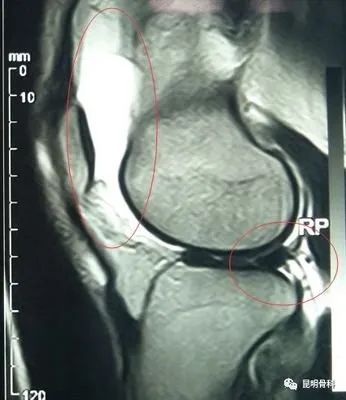

膝關(guān)節(jié)滑膜炎是我們?nèi)粘I钪谐R姷囊环N疾病,引起膝關(guān)節(jié)滑膜炎的原因有很多,比如創(chuàng)傷、感染等等,但最常見病因是創(chuàng)傷。

創(chuàng)傷性膝關(guān)節(jié)滑膜炎,是因為膝關(guān)節(jié)受到急性或慢性外力,造成滑膜損傷,引起滑膜充血、腫脹、膝關(guān)節(jié)腔積液。這種情況多因膝關(guān)節(jié)慢性、反復(fù)勞損、劇烈運動、超負(fù)荷運動等引起。目前門診接診很多因參加健步走出現(xiàn)膝關(guān)節(jié)腫脹疼痛患者,就是因為慢性反復(fù)勞損引起的,所以我們要根據(jù)自身情況適當(dāng)鍛煉。

首先建議做膝關(guān)節(jié)核磁共振檢查,一般情況需要臥床休息,下肢抬高,必要時給予下肢支具外固定。膝關(guān)節(jié)腔積液較多時,可行關(guān)節(jié)穿刺抽液,并關(guān)節(jié)注射藥物,能夠快速緩解關(guān)節(jié)腫脹疼痛,口服非甾體類消炎鎮(zhèn)痛藥物,膝關(guān)節(jié)局部進(jìn)行膏藥外敷、理療等。